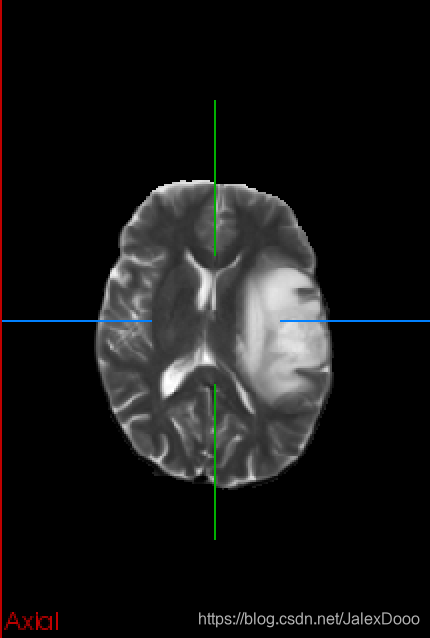

用在了大脑胶质瘤分割上,2D的处理方式,论文也是2D的处理形式,实在差劲;然后改成3D处理,还是差劲。

2D处理